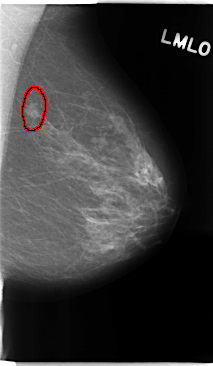

C_0135_1.RIGHT_MLO

C_0135_1.LEFT_MLO

LEFT_MLO LINES 4752 PIXELS_PER_LINE 2760 BITS_PER_PIXEL 12 RESOLUTION 50 OVERLAY

FILE: C_0135_1.LEFT_MLO.OVERLAY

TOTAL_ABNORMALITIES 1

ABNORMALITY 1

LESION_TYPE MASS SHAPE IRREGULAR MARGINS MICROLOBULATED

ASSESSMENT 4

SUBTLETY 5

PATHOLOGY MALIGNANT

TOTAL_OUTLINES 1

BOUNDARY